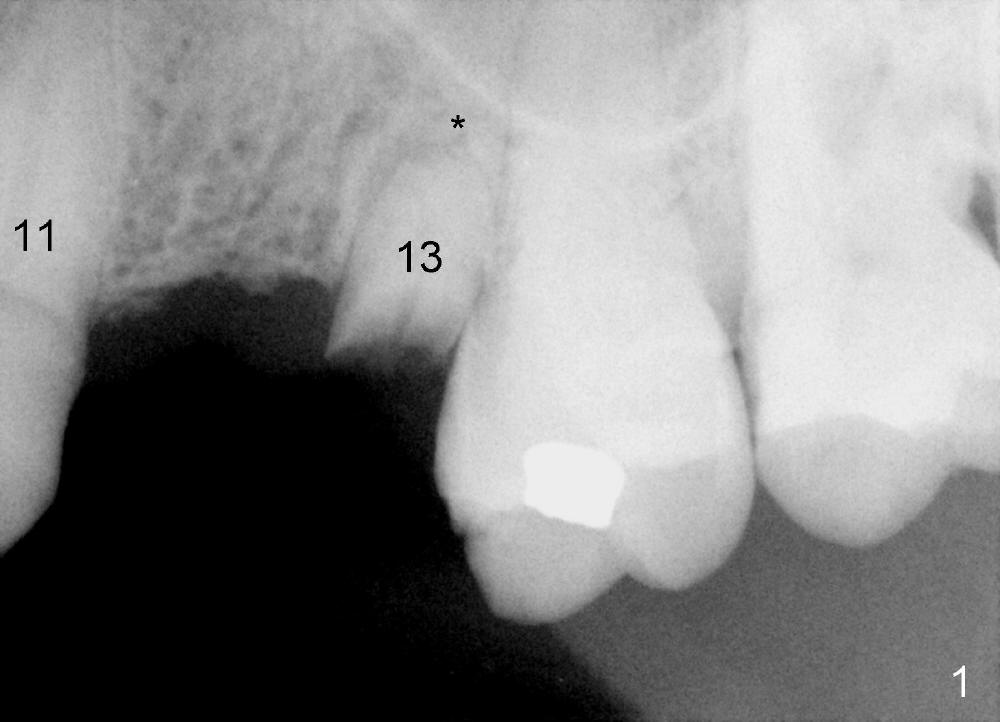

A 77-year-old man dislodged a bridge involving the teeth #11-13 5 years ago (Fig.1). It was recemented. Recently it is dislodged again. The patient agrees to have a definitive treatment to support the lower right quadrant reconstruction.

The anterior retainer is kept as a crown at #11 (Fig.2: C), whereas the residual root at the site of #13 is extracted with apical perforation (Fig.3 ^). It is confirmed by Fig.4 (<). To close the perforation, an osteotomy is initiated on the palatal wall of the socket with a 2 mm osteotome (Fig.5 insert: circle). As the osteotomy is being enlarged by a 3 mm osteotome, the bone between the original socket and the osteotomy is being pushed buccally. The former is being closed (Fig.5). The osteotomy is finished with combination of osteotomes and reamers. Fig.6 shows that a 5x14 mm tap is inserted at the site of #13 and that the sinus floor is lifted. In fact the sinus membrane is partially torn at the osteotomy, which is repaired by insertion of Colla-form Dressing (Impladent), followed by autogenous bone (harvested from reamers) mixed with Osteogen (Impladent). A 5x14 mm implant is placed at the site of #13 with insertion torque more than 60 Ncm (Fig.7: I). An incision is made at the site of #12 to start osteotomy with insertion of a parallel pin (Fig.7 P). A 3 mm reamer is kept in place for position confirmation (Fig.8 R). Due to ridge atrophy (Fig.2 arrowheads), a much smaller, but longer implant is placed at the site of #12 (Fig.9: 4x17 mm). The autogenous bone harvested from #12 osteotomy is placed in the buccal gap of #13, followed by insertion of Colla-form Dressing (Fig.10 M). To protect the membrane, a short abutment (4x3 mm) is temporarily placed (Fig.9,10 A) and perio dressing (Fig.9 D) is applied around the abutment and the interproximal areas of the neighboring teeth. Usually perio dressing dislodges around 1 week postop, particularly for a large edentulous space. In this case, the dressing is quite stable 11 days postop: the abutment (Fig.11 A) appears to contribute to retention of the dressing (D).